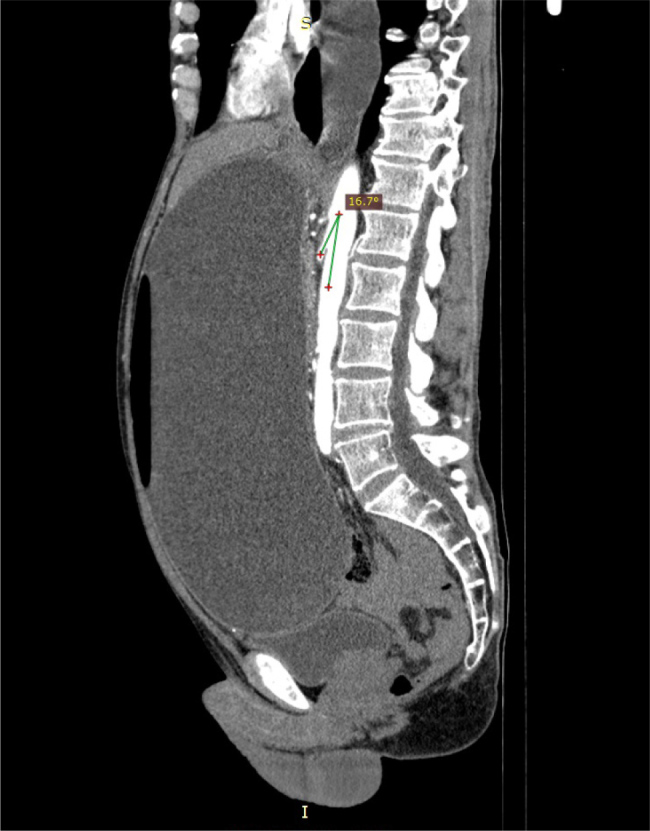

Case presentation: We report the case of a 62-year-old man with a known history of achalasia, previously managed with botulinum toxin injections. He presented with progressively worsening abdominal bloating, unintentional weight loss, and abdominal discomfort. Endoscopy revealed a strikingly dilated oesophagus and stomach, filled with nearly 9 litres of fluid. Further imaging with computed tomography angiography showed a narrowed aortomesenteric angle measuring just 16.7°, consistent with a diagnosis of SMA syndrome. Remarkably, despite the massive distension, no perforation was identified.

Discussion: This case highlights a rare but important overlap between achalasia and SMA syndrome, leading to extreme gastric dilatation in the absence of rupture. Despite the extreme degree of gastric dilatation observed on both endoscopy and imaging, the stomach wall remained intact, and there were no signs of ischemia or perforation. Although SMA syndrome may occur secondary to other health conditions, this case underscores how variable and potentially dangerous this dual pathology can be.